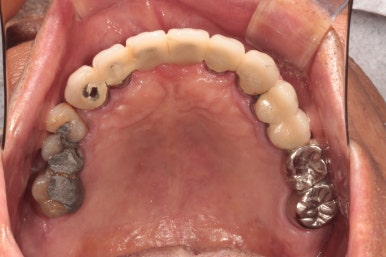

왼쪽: 위턱 교합면, 오른쪽: 아래턱 교합면

처음 치과에 방문하시면, 어떤 이를 뺄지 결정하는 것이 가장 중요합니다.

어떤 치료를 받으시냐에 따라 어떤 치아를 뺄지도 조금 달라지죠.

보통 임플란트 치료를 받으신다면 최대한 치아를 유지할 수 있고, 틀니 치료를 받으신다면 애매한 치아는 모두 빼게되는 경향이 있습니다.

위턱 교합면에서도,

아래턱 교합면에서도 아주 정갈하고 깔끔하게 임플란트 크라운이 잘 제작된 것을 보실 수 있습니다.

사실 어디하나 흠잡을데 없다고 생각합니다....호호...